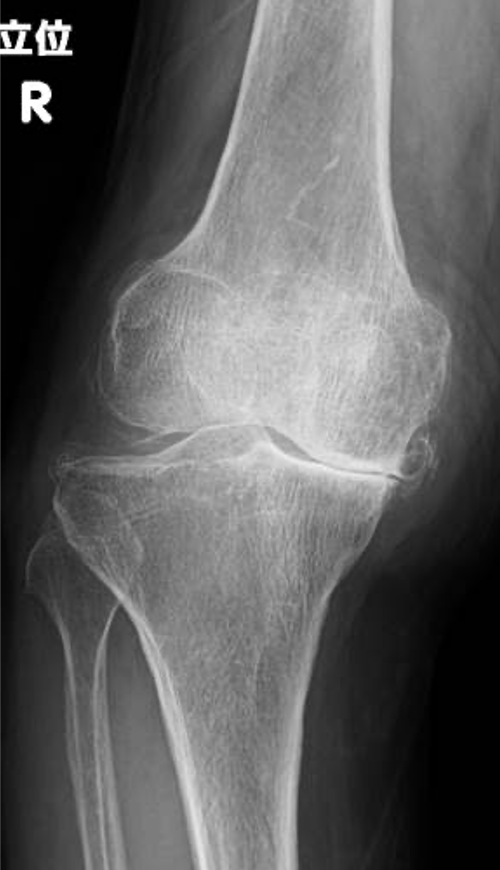

変形性膝関節症は一次性と原因疾患に続発する二次性に分類されます。わが国では年齢による退行性変化を主因とする一次性が多く、軟骨のすり減り、骨棘(骨のとげ)を伴い、多くは内反変形(O脚)を呈します。女性に多く、特に肥満との関連が強いといわれています。膝関節には歩行するだけで体重の3倍の力がかかるといわれており、病状の予防や進行を抑えるためには体重のコントロールが最も重要です。症状には波がありますが、次第に進行し、変形も悪化してきます。まずは保存加療を行いますが、痛みが強く日常生活に支障をきたすようだと、我慢するメリットはありません。痛みのない脚でより良い人生を送るために手術という選択肢もありますので、痛みで悩まれている場合は早めにご相談ください。

〈手術前のレントゲン〉

右ひざ

左ひざ

〈手術後のレントゲン〉

右TKA後

左TKA後